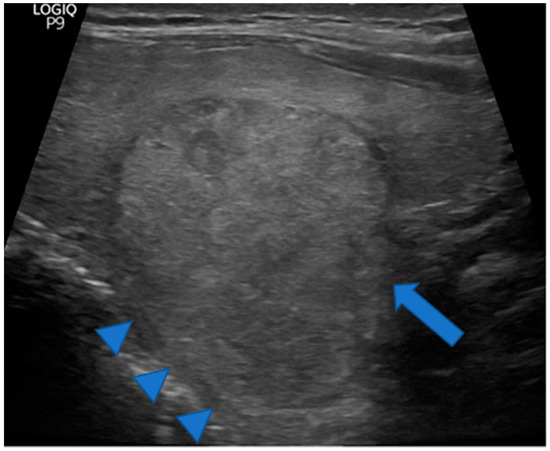

Figure 5.

Huge TTW nodule extending into a prominent posterior horn (arrowheads). Note the thyroid parenchyma extending along the cranial portion of the nodule (arrowheads) but not along the caudal portion (arrow) arguing for a pre-existing posterior horn. A pre-existing posterior horn may have channeled the way for nodule growth causing its taller than wide shape. The nodule was benign at cytology.